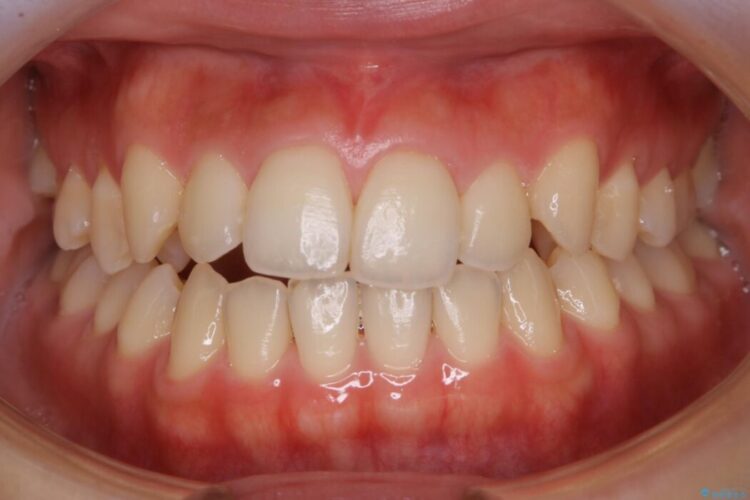

治療後写真を見ても歪みが解消され、歯列弓がきれいに整ったのが分かると思います。インビザラインをしっかりと装着されていたこともあり、矯正としては短期間の治療となりました。